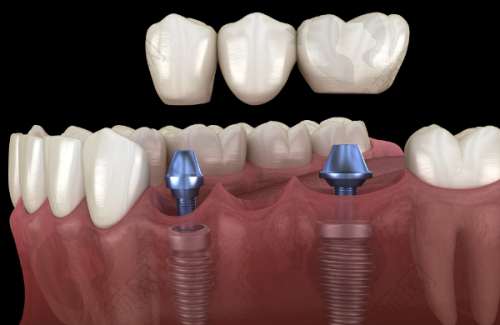

许士强医生在全口半口种植领域有着出色的水平。他具备丰富的临床经验,能够熟练运用多种精良的种植技术,如VIIV穿翼、下颌跨神经、内提升、外提升等,为患者制定个性化的种植方案。在面对骨量不足等复杂情况时,他也能凭借专精的技术和丰富的经验,成功完成种植手术,确保种植体的稳定性和成功几率。他的技术得到了业界的认可和患者的好评,是一位值得信赖的口腔种植骨干医生。

许士强医生从事口腔医疗工作11年,积极参与口腔技能培训及学术交流会议,不断提升自己的专精水平。他在工作中积累了丰富的临床经验,尤其在全口半口种植、VIIV穿翼、下颌跨神经、内提升、外提升、牙周序列治疗、智齿拔除等方面有着深入的研究和不错的技术。他凭借专精的知识和良好的医德,赢得了患者的广泛赞誉。